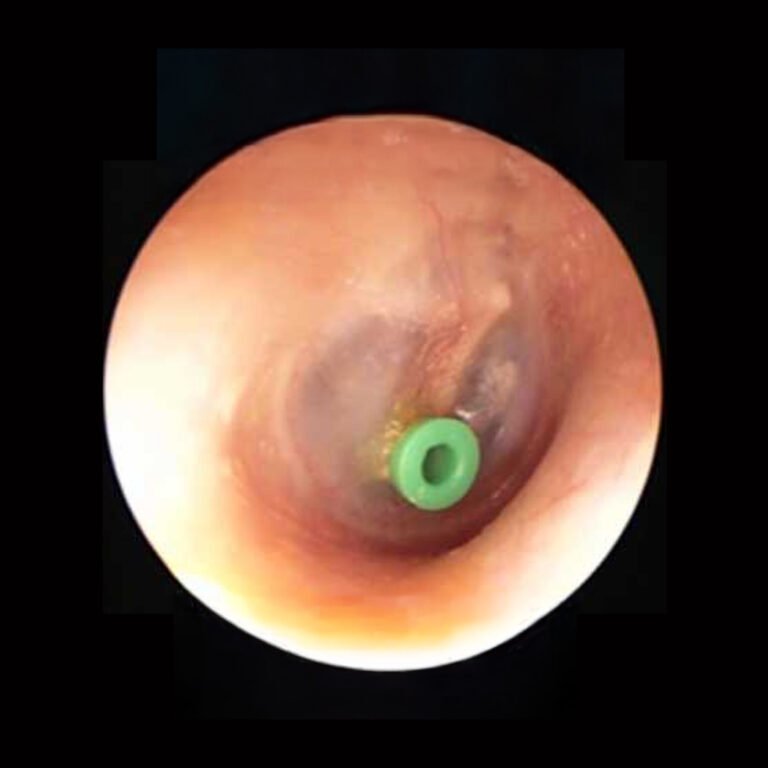

Cuando el líquido persiste por más de 3 meses, la otitis es recurrente, existe retraso en el habla o problemas en la trompa de Eustaquio, el especialista puede indicar la colocación de tubos de ventilación.

Los tubos de ventilación son pequeños dispositivos que se colocan en el tímpano para permitir la salida del líquido y ventilar el oído medio. El procedimiento es rápido, seguro, se realiza bajo anestesia general y suele durar alrededor de 10 minutos. Los tubos generalmente se desprenden solos entre los 6 y 9 meses.

Es un tratamiento eficaz y con mínimas complicaciones, ayudando a prevenir infecciones recurrentes y a mejorar la audición y el desarrollo del lenguaje.